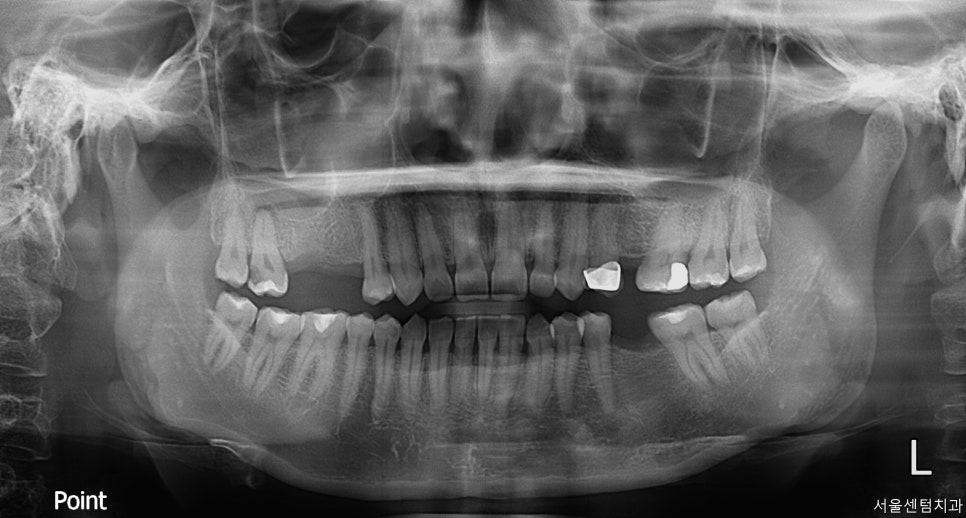

정확한 진단을 위해서는 파노라마 촬영과

CBCT 촬영을 진행을 했는데요.

이 과정이 꼭 필수적인 이유는

육안으로 보이지 않는 뼈의 상태와

신경의 위치, 상악동까지의 거리 등을

정밀하게 파악 할 수 있기 때문입니다.

오른쪽 위 첫번째 큰 어금니 부위 CT

치료시작 전 전체 치아 사진